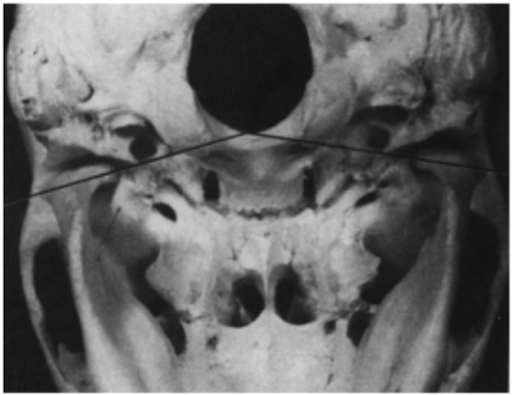

Lồi cầu thuôn, kích thước theo chiều ngang (ngoài – trong) từ 15 – 20 mm, theo chiều trước sau là 8 – 10 mm. Đầu ngoài và đầu trong của lồi cầu tận hết bởi các cực: cực ngoài và cực trong (Hình 1). Đường nối hai cực lồi cầu kéo dài sẽ đi về phía trong và phía sau, gặp nhau ở vùng bờ trước lỗ chẩm, tạo thành một góc khoảng 145-160° (Hình 2). Đường nối hai cực của lồi cầu như vừa mô tả cũng có hướng song song với đường nối các múi ngoài và trong tương ứng của các răng sau. Cực ngoài ngắn (nên ở gần cổ lồi cầu hơn cực trong), khá tù và thường gồ ghề ở nơi bám của đĩa khớp, dây chằng thái dương hàm bám vào một củ nhỏ (củ dưới lồi cầu ngoài). Cực trong dài nên ở xa cổ lồi cầu và cũng gồ ghề ở nơi bám của đĩa khớp và bao khớp.

Hình 2: Đường nối hai cực lồi cầu kéo dài đi về phía trong và phía sau, gặp nhau ở vùng bờ trước lỗ chẩm.